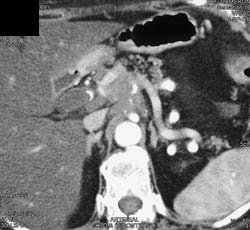

Hepatic Artery Aneurysm